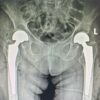

Premieră medicală în județul Sibiu: artroplastie bilaterală de șold realizată într-un singur timp operator, la SCJUS DESCARCĂ DOCUMENT